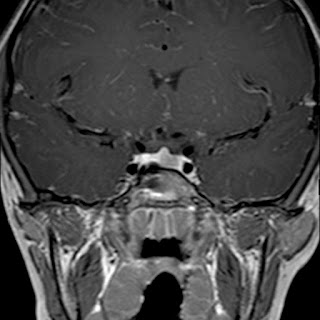

Caso neurorradiología

Paciente de 60 años con cuadro de 1 semana de evolución consistente en tropiezos frecuentes y alteración en la movilidad del miembro

inferior derecho. No refiere

cefalea u otros síntomas asociados, no pérdida de peso, no náuseas o emesis, no

sudoración nocturna. Antecedentes de hipertensión arterial y diabetes.

Resonancia magnética